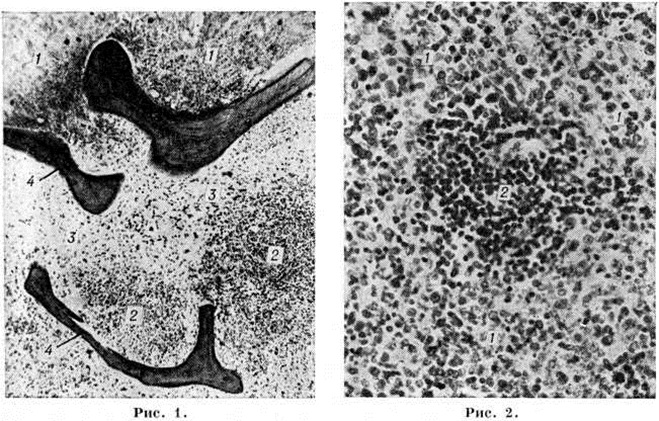

В костном мозге, по данным трепанобиопсии, на первых стадиях заболевания скопления бластных клеток являются очаговыми, в достаточном количестве обнаруживаются элементы деятельного костного мозга. Нередко наблюдаются острые расстройства кровообращения, участки гипоплазии, могут обнаруживаться некрозы. Прогрессирование заболевания характеризуется увеличением числа и размеров лейкозных разрастаний, их слиянием, а затем диффузной инфильтрацией ткани костного мозга. Количество нормальных кроветворных клеток заметно уменьшается. Часто имеется инфильтрация надкостницы, возможно распространение процесса в окружающие мягкие ткани. Развитие лейкозных разрастаний сопровождается выраженным рассасыванием костной ткани, преимущественно по типу гладкой резорбции. Очень редко в этом процессе принимают участие остеокласты. Вследствие частичного, а местами и полного рассасывания костных балок происходит значительное расширение костномозговых полостей, истончение, а в некоторых участках разрушение кортикального слоя. В раннем детском возрасте резкие изменения наблюдаются в зоне энхондрального окостенения. При острых Лейкозы редко отмечается очаговое новообразование атипичной костной ткани, богатой остеоидом, разрастание фиброзной ткани. Наряду с мелкими фокусами некроза иногда возникают обширные инфарктообразные коагуляционные некрозы, определяемые макроскопически в виде жёлто-белых сухих участков; в окружности наблюдаются кровоизлияния, возможно скопление макрофагов (рисунок 1). В области лейкозных разрастаний нередко обнаруживается истончение и частичный распад ретикулярных волокон. Описаны наблюдения с очаговым или диффузным миелофиброзом, который чаще выявляется при миелобластном Лейкозы. В таких случаях при пункции обычно не удаётся получить костный мозг и для установления диагноза необходимо исследование материала трепанобиопсии.

Лейкозная инфильтрация ткани селезёнки и лимфатических, узлов сопровождается уменьшением размеров (рисунок 2) и числа фолликулов вплоть до полного их исчезновения. В селезёнке часто наблюдается инфильтрация трабекул с разволокнением стенок трабекулярных сосудов, с деформацией и сужением их просвета, имеются поля кровоизлияний. В лимфатических, узлах вначале возникают очаговые инфильтраты, которые по мере прогрессирования болезни увеличиваются в размерах, и поражение становится диффузным.

Острый лимфобластный лейкоз, особенно у детей, чаще всего характеризуется массивным поражением всех групп лимфатических, узлов, селезёнки, вилочковой железы, нередко со значительным их увеличением. В вилочковой железе лейкозная инфильтрация располагается внутри долек и обусловливает разрушение эпителиального ретикулума. В лёгких разрастания локализуются преимущественно в стенках и окружности бронхов, в печени — в области портальных полей. При распространённом процессе пролифераты выявляются в желудочно-кишечные тракте, центральная нервная система, почках, половых органах и другие В детском и юношеском возрасте обширные узловатые разрастания чаще возникают при данной форме и локализуются главным образом в вилочковой железе и лимфатических, узлах переднего средостения. Нередко они распространяются на перикард, плевру, ткань лёгких, что приводит к образованию массивного опухолевого конгломерата. Разрастания в костном мозге и других органах состоят из бластных клеток лимфоидного происхождения, которым свойственно высокое ядерно-цитоплазматическое соотношение.

Острый миелобластный лейкоз в развёрнутой стадии болезни характеризуется выраженной лейкозной инфильтрацией костного мозга и других органов. В печени лейкозные разрастания локализуются в синусоидных капиллярах и в области портальных трактов. Аналогичное расположение инфильтратов имеется и при других более редких формах острого Лейкозы (монобластном, миеломонобластном, недифференцируемом, промиелоцитарном и другие), поэтому данный признак не может служить основанием для разграничения форм острого Лейкозы В лёгких лейкозная инфильтрация обычно выявляется по ходу межальвеолярных перегородок с выходом бластных клеток в просветы альвеол (рисунок 3), возможна локализация и в окружности бронхов, сосудов, междольковых перегородках. У детей при этой форме Лейкозы лейкозные разрастания в вилочковой железе располагаются в соединительнотканных прослойках, сдавливают дольки, что сопровождается увеличением количества аргирофильных волокон. У взрослых типично развитие множественных узлов в надкостнице плоских и трубчатых костей, почках, печени, половых железах, жировой клетчатке (подкожной, ретробульбарной, клетчатке большого сальника и малого таза), иногда в коже, конъюнктиве, твёрдой мозговой оболочке и костном мозге. В ряде случаев в области опухолевых узлов и системных поражений имеется зелёное окрашивание ткани (хлоролейкоз). Аналогичные изменения могут выявляться и при Лейкозы у детей.

При остром мегакариобластном лейкозе в костном мозге выявляется большое количество атипичных мегакариоцитов и мегакариобластов, которые диффузно рассеяны в ткани, а местами образуют скопления (рисунок 4). Такие же клетки в значительном количестве содержатся в ткани и синусах селезёнки, лимфатических, узлов, просветах мелких сосудов печени, лёгких и других органов.

При микроскопическом исследовании в костном мозге преобладают незрелые и зрелые клетки гранулоцитарного ряда (рисунок 5), соотношение которых может варьировать. По данным трепанобиопсий, в начальной стадии заболевания ещё в достаточном количестве сохраняются элементы эритропоэтического и мегакариоцитарного ряда. По мере прогрессирования процесса их число снижается, исчезают жировые клетки. Характерны глубокие изменения в строме в виде сочетания процессов деструкции с увеличением количества фибробластов, аргирофильных и иногда коллагеновых волокон. Изучение костного мозга методом трепанобиопсии в динамике свидетельствует о том, что миелофиброз постепенно нарастает и бывает более выражен у больных с повторными ремиссиями и обострениями заболевания. В отдельных случаях в костном мозге имеют место обширные очаги некроза; постоянно наблюдается выраженное рассасывание костной ткани. В селезёнке и лимфатических узлах в развёрнутой стадии болезни обнаруживается диффузная инфильтрация миелоидными элементами, атрофия лимфатической ткани. Лейкозное поражение селезёнки часто сопровождается выраженным в различной степени фиброзом красной пульпы, образованием полей склероза, что наряду с инфильтрацией и полнокровием является причиной увеличения её веса. Для хронический миелолейкоза характерна локализация лейкозных инфильтратов в печени по ходу синусоидных капилляров (рисунок 6), в лёгких — в области межальвеолярных перегородок. Нередко наблюдается инфильтрация стенок мелких бронхов, сосудов, плевры. Реже, чем при острых Лейкозы очаги лейкозной инфильтрации возникают в почках, мышце сердца, в стенках желудочно-кишечные тракта, в оболочках и веществе головного мозга, коже, железах внутренней секреции и других органах.

Микроскопически в костном мозге обнаруживается системное разрастание лимфоцитов. При обострении процесса наряду со зрелыми лимфоцитами выявляются пролимфоциты и лимфобласты. В костном мозге выделяют три типа инфильтрации: диффузную, диффузно-очаговую, очаговую. При первых двух типах инфильтрации расширенные полости костного мозга содержат значительное количество лимфоцитов, диффузно рассеянных в ткани или образующих наряду с этим компактные скопления (диффузно-очаговый тип). В отличие от других форм Лейкозы даже при массивной инфильтрации в костном мозге сохраняются небольшие очаги нормального кроветворения, не исчезают полностью жировые клетки. Для хронический лимфолейкоза характерно резкое рассасывание костной ткани и отсутствие признаков её новообразования. Данные прижизненного гистологический исследования костного мозга показывают, что очаговый тип инфильтрации наблюдается в ранние стадии заболевания. В отличие от лимфоидных узелков, выявляемых в норме в костном мозге, а также от реактивной нодулярной лимфоидной гиперплазии, сопутствующей ряду заболеваний, при хронический лимфолейкозе очаговые скопления лимфоцитов характеризуются довольно крупными размерами, лишены чётких границ, имеют тенденцию к слиянию, содержат наряду со зрелыми лимфоцитами пролимфоциты и лимфобласты. Разграничение этих изменений с метастазами в костный мозг лимфоцитарной лимфосаркомы ввиду сходности морфологический картины основывается на особенностях клинические, проявлений заболевания. При развёрнутой картине хронический лимфолейкоза в лимфатических, узлах обнаруживается диффузная инфильтрация ткани лимфоцитами с полным стиранием рисунка, которая может проникать через капсулу в окружающую жировую клетчатку. В селезёнке в некоторых случаях видны резко увеличенные в размерах фолликулы без центров размножения, сливающиеся друг с другом, однако чаще имеется полное стирание рисунка вследствие диффузной инфильтрации ткани лимфоцитами. Нередко встречаются поля склероза. В печени обширные скопления лимфатических, клеток располагаются главным образом в области портальных полей (рисунок 7), но могут встречаться и в синусоидных капиллярах. В зонах инфильтрации нередко имеет место разрастание аргирофильных и коллагеновых волокон. Часто наблюдается расширение желчных капилляров и застой желчи, дистрофия, частичный некробиоз и некроз гепатоцитов. В лёгких разрастания локализуются в стенках бронхов, что приводит к нарушению их дренажной функции и способствует развитию пневмоний. Могут наблюдаться участки массивной лейкозной инфильтрации ткани лёгкого. При микроскопии гнездные скопления лимфоцитов нередко обнаруживаются в строме почек, оболочках и мышце сердца, половых железах, жировой клетчатке и так далее. Очень редко встречается специфическая инфильтрация оболочек и вещества головного мозга. Частой находкой является скопление лимфоцитов в просветах сосудов различных органов, особенно при значительном лейкоцитозе. В отдельных случаях при обострении хронический лимфолейкоза возникают массивные опухолевые разрастания, исходящие главным образом из лимфатических, узлов. Опухолевые массы состоят из крупных недифференцированных клеток с уродливыми ядрами, нередко в них обнаруживаются участки некроза, кровоизлияния. Характерен резко выраженный инфильтрирующий рост.